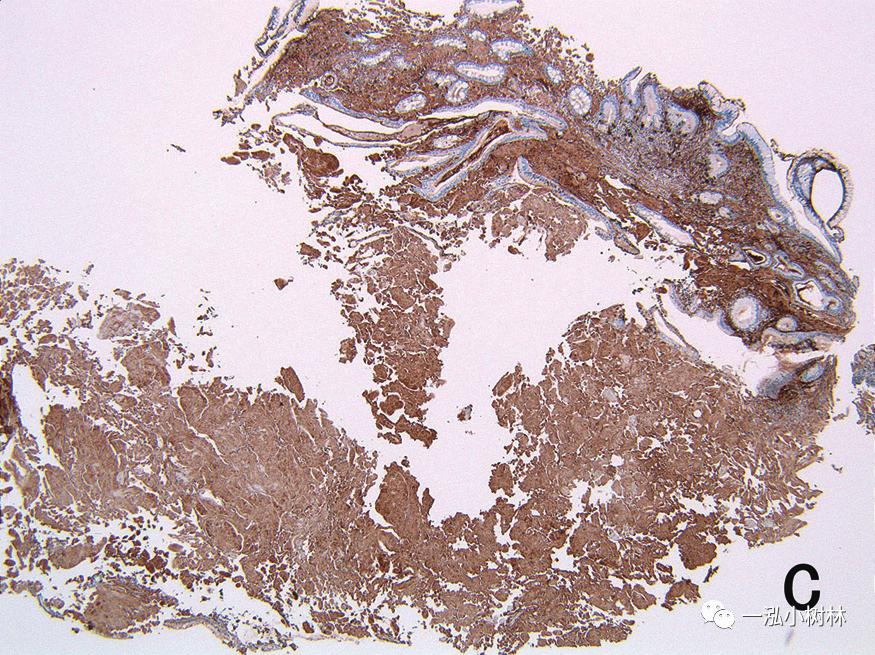

病理组织检查(图4):胃活检标本:弱嗜酸性的均质无结构物质的沉积。该物质通过DFS染色,在之后的高锰酸处理中保持染色性,怀疑为AL型淀粉样变性,但在之后的免疫染色中为转位蛋白阳性,认为SSA的可能性很高。在食管、十二指肠的活检标本中没有发现淀粉样蛋白的沉积。

图4c 胃活检标本病理组织像(TTR×40),淀粉样蛋白在TTR的免疫染色中显示阳性。

以胃为首的消化道淀粉样变性中,沉积的淀粉样前体蛋白的种类和内镜观察结果有相关性。在AA型淀粉样变性中,淀粉样蛋白沉积在以黏膜固有层为中心的黏膜浅层,一般认为,呈现糜烂和溃疡等黏膜表面变化的情况很多。AL型淀粉样变性中,淀粉样蛋白在黏膜下层和固有肌层的比较深层堆积成块状,在内镜观察中,很多情况下可以看到黏膜下肿瘤样隆起和皱襞的肥厚。在怀疑为SSA型的胃淀粉样变性中,迄今还没有进行NBI放大观察的报告。在本病例中,进行了包括NBI放大观察在内的详细的内镜观察,在胃黏膜的褪色区域发现了散在的小隆起和血管的扩张、蛇形、密度的降低。来自TTR的淀粉样蛋白容易沉积在黏膜下层的小的血管壁上,具有容易沉着于固有肌层和浆膜下层的特征。在本病例中,在NBI放大观察中发现了白区的不明确化。白区显示了在NBI观察中在白色边缘形成的黏膜构造,一般认为NBI光在腺窝上皮的散射导致。在活检标本中(图4),淀粉样蛋白以胃黏膜下层为中心沉积,因此,在淀粉样蛋白沉积部位,NBI光的散射降低,可以认为白区变得不明确。另外,也发现了黏膜表层的微小血管的扩张、蛇行、密度的降低。在活检标本中,黏膜下层没有包含明显的血管结构,另外,本病例没有对H.p的感染进行检索,但由于患者年龄和淀粉样蛋白沉积不太明显的部分的胃黏膜出现萎缩,因此推测伴有H.p感染的可能性很高。在消化道淀粉样变性病中,为了确认识别沉着的淀粉样变性,有必要进行组织活检。如果考虑淀粉样变性应行NBI放大观察是非常有效的。